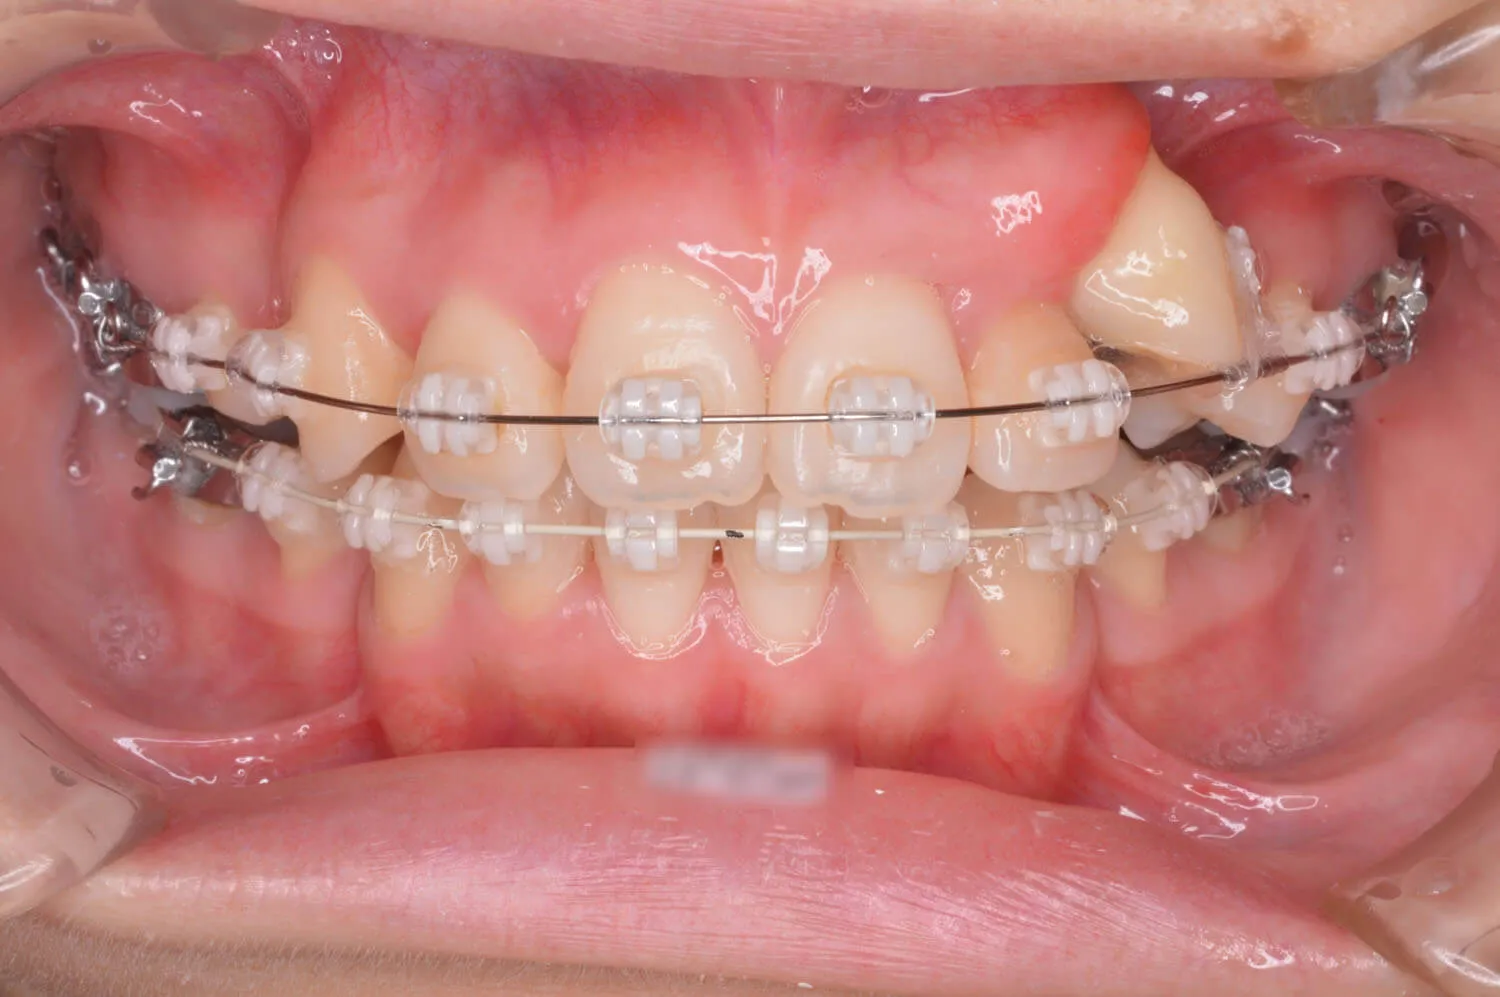

ブラケット装置が装着されました。

犬歯のけん引をはじめました。